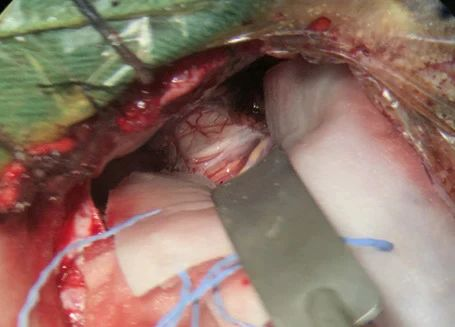

病人多发脑海绵状血管畸形,本次出血部位位于桥脑。第一次出血,术前偏瘫,转入我病房时为出血一月左右,采取颞下岩前入路切除脑干病变,术后病人肢体肌力较术前有提高,目前尚未出院。

本次手术资料: